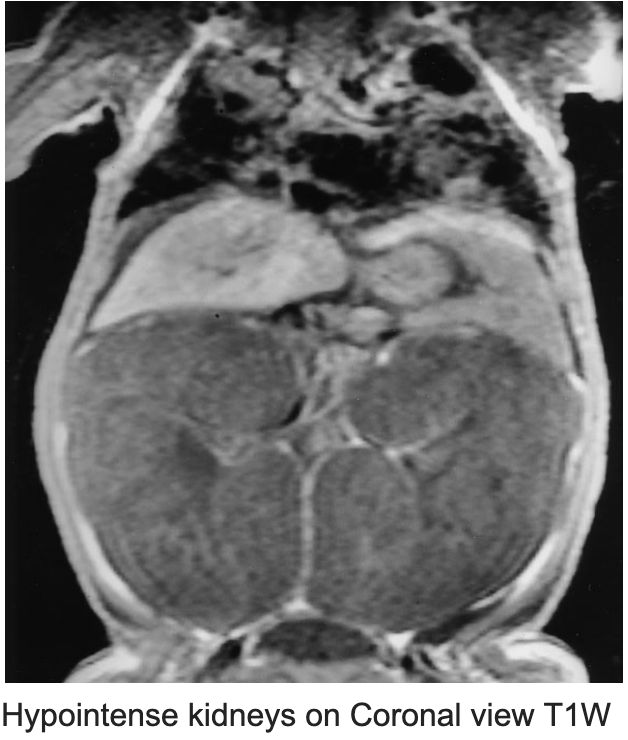

12/ In cases with ambiguous findings on ultrasound, MRI confirms the diagnosis.

🔶Hyperintense enlarged kidneys on T2W

🔶RARE-MRI (rapid acquisition with relaxation enhancement)- microcystic dilatation & hyperintense, linear radial pattern in the cortex & medulla.

PMID 10755752